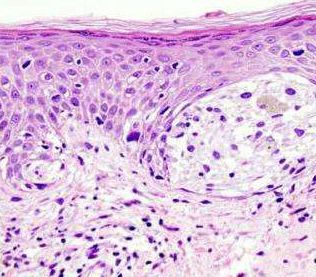

有黑色素细胞在皮肤中积累,黑色素是由黑色素细胞分泌的...